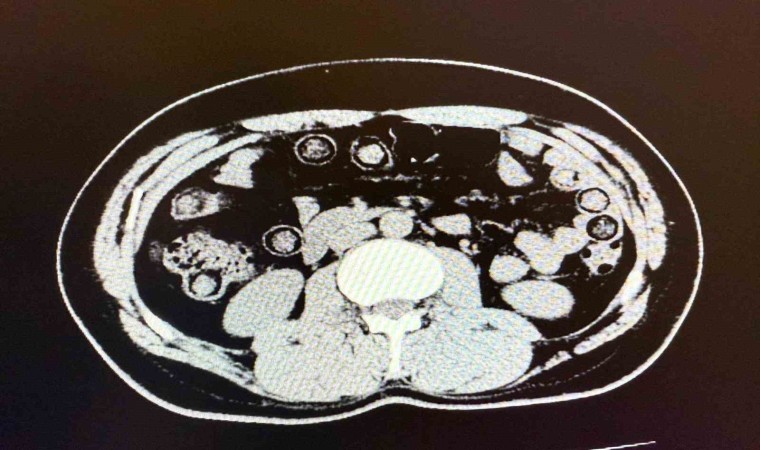

Muş Valiliği tarafından yapılan açıklamada, “Narkotik Suçlarla Mücadele Şube Müdürlüğümüzce uyuşturucu madde sevkiyatına engel olmak için yapılan çalışmalar neticesinde İran uyruklu 2 şahsın şehirlerarası yolcu otobüsü ile illere uyuşturucu madde nakli gerçekleştirebilecekleri değerlendirilmiş, 6 Aralık günü saat 11.30 sıralarında şüpheli şahısların görevlilerimizce yapılan sorgulamasında uyuşturucu madde naklettikleri yönünde kuvvetli şüphe oluşmuştur. Hastanede yapılan iç beden muayeneleri sırasında çekilen tomografi görüntülerine göre uyuşturucu madde yuttukları tespit edilmiştir. Hastanede yapılan tespit sonrasında şahısların midelerinde toplam 94 adet kapsül içerisinde daralı ağırlıkları 928 gram gelen metamfetamin maddesi ele geçirilmiştir. Şüpheli şahıslar hakkında ‘uyuşturucu ve uyarıcı madde ticareti’ suçundan işlem yapılmak üzere Cumhuriyet Başsavcılığına intikal ettirilmiş ve çıkarıldıkları mahkemece tutuklanmışlardır” denildi.